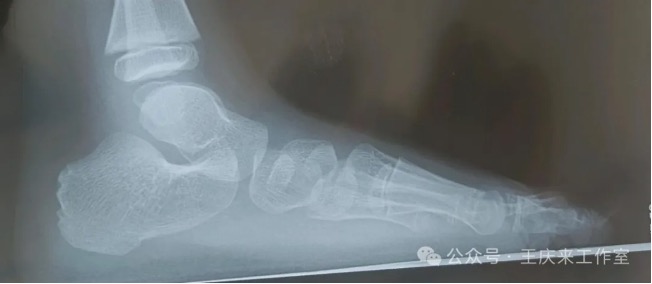

扁平足的检测方法主要有两种:足印法和影像学检查。足印法简单易行,通过观察足印最窄区与足长的比例,可以初步判断是否存在扁平足。影像学检查则更为精确,通过足部X线检查,可以测量足弓角度,明确足弓结构,从而准确判断是否存在扁平足。